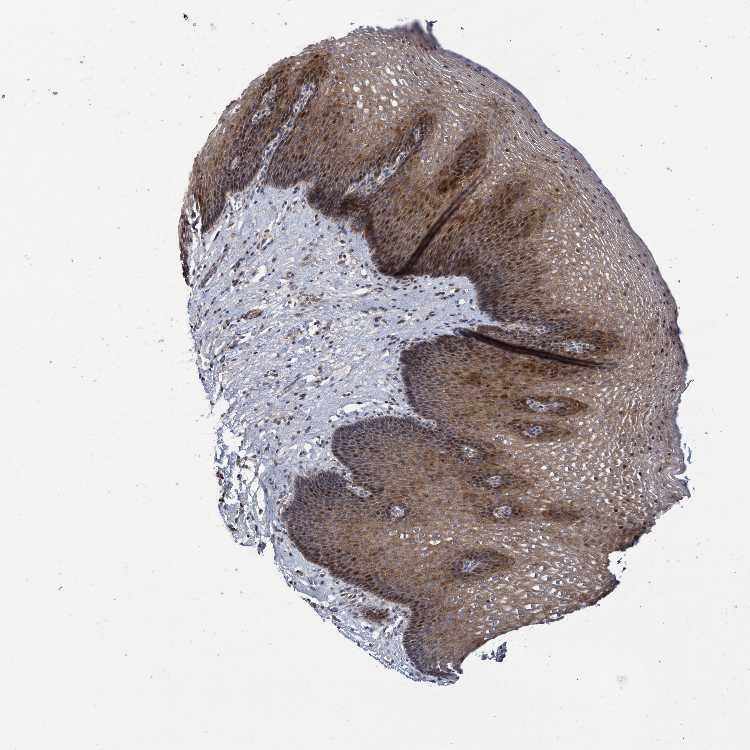

ESOPHAGUS - Antibody stainingi

Antibody staining in the annotated cell types in the current human tissue is reported as not detected, low, medium, or high, based on conventional immunohistochemistry profiling in selected tissues. This score is based on the combination of the staining intensity and fraction of stained cells.

Each image is clickable and will lead to virtual microscopy that enables deeper exploration of all samples and also displays staining intensity scores, fraction scores and subcellular localization as well as patient and tissue information for each sample.

Antibody HPA023106

Squamous epithelial cells Medium